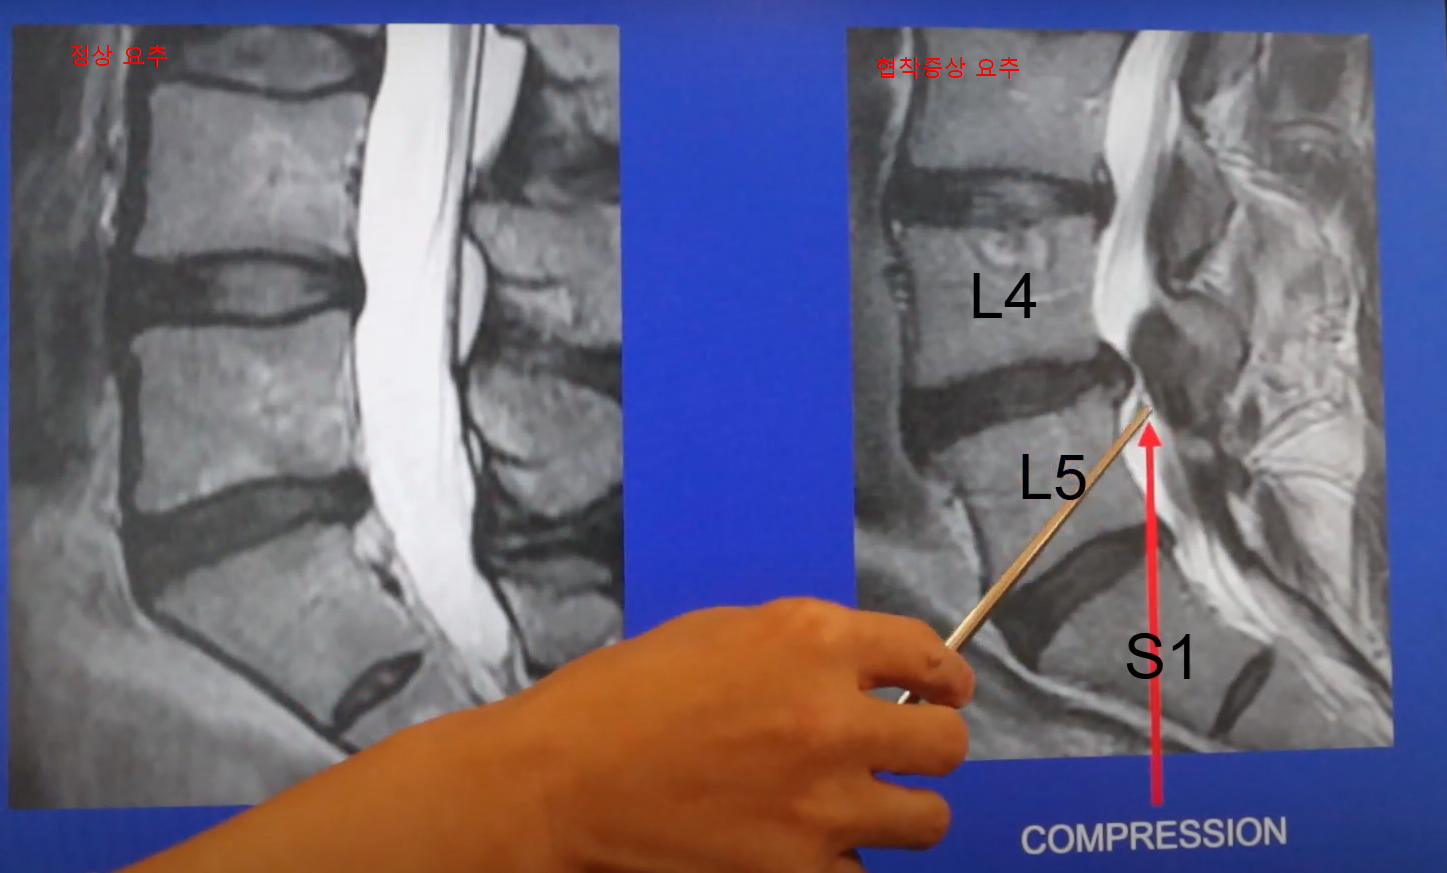

척추관 협착증(Spinal Stenosis)은 척추 내부의 신경 통로(척추관)가 좁아지면서 신경이 압박되어 통증, 저림, 근력 약화 등의 증상을 유발하는 질환입니다.

📌 척추 내부의 신경 통로(척추관)가 좁아지면서 신경이 눌려 통증 및 신경 증상을 유발하는 질환

② 척추 디스크 질환 (Herniated Disc, Bulging Disc)

- 허리디스크(추간판 탈출증) – 디스크가 돌출되어 척추관을 좁히고 신경을 압박

- 디스크가 부풀어 오르거나 변형되면서 척추관이 좁아질 수 있음